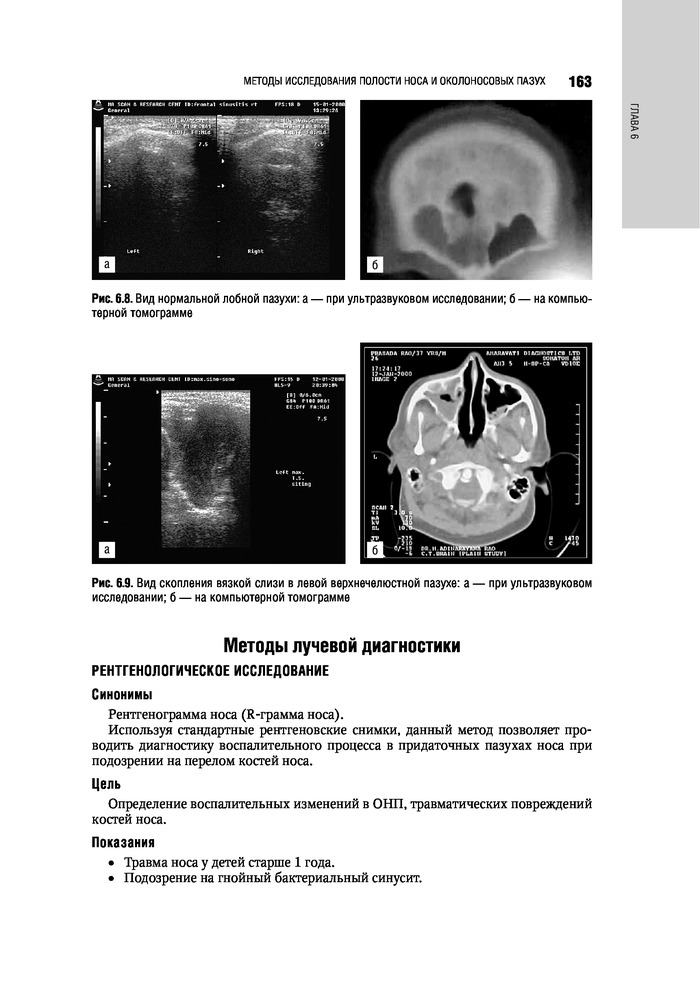

%text%